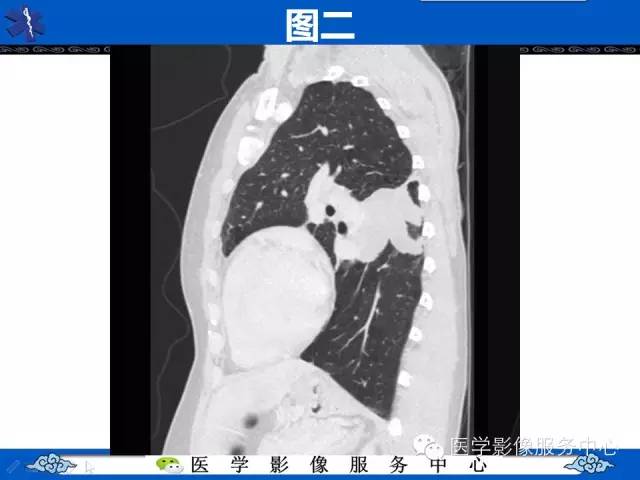

【病例】胸壁弹力纤维瘤1例CT影像表现